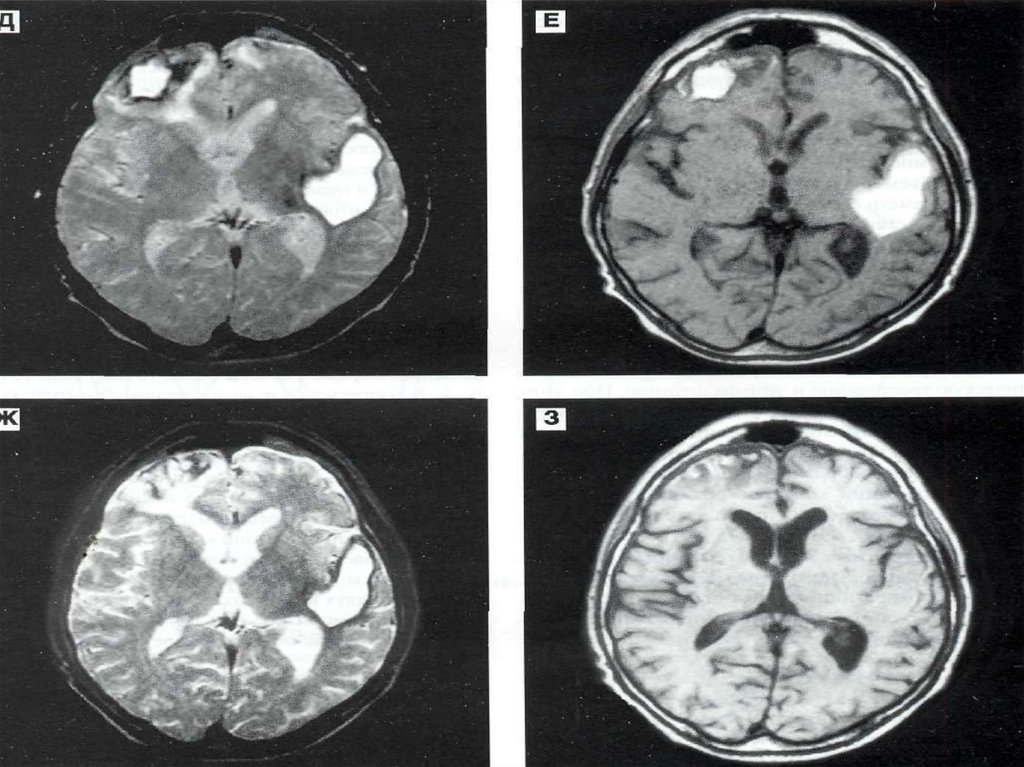

Голова:

Аномалии и пороки развития ГМ;

Травмы головы;

Опухоли ГМ;

Заболевания сосудов ГМ;

Заболевания ЛОР-органов и глазниц;

Заболевания височной кости;

Заболевания слюнных желёз;

В послеоперационном периоде для оценки состояния ГМ.